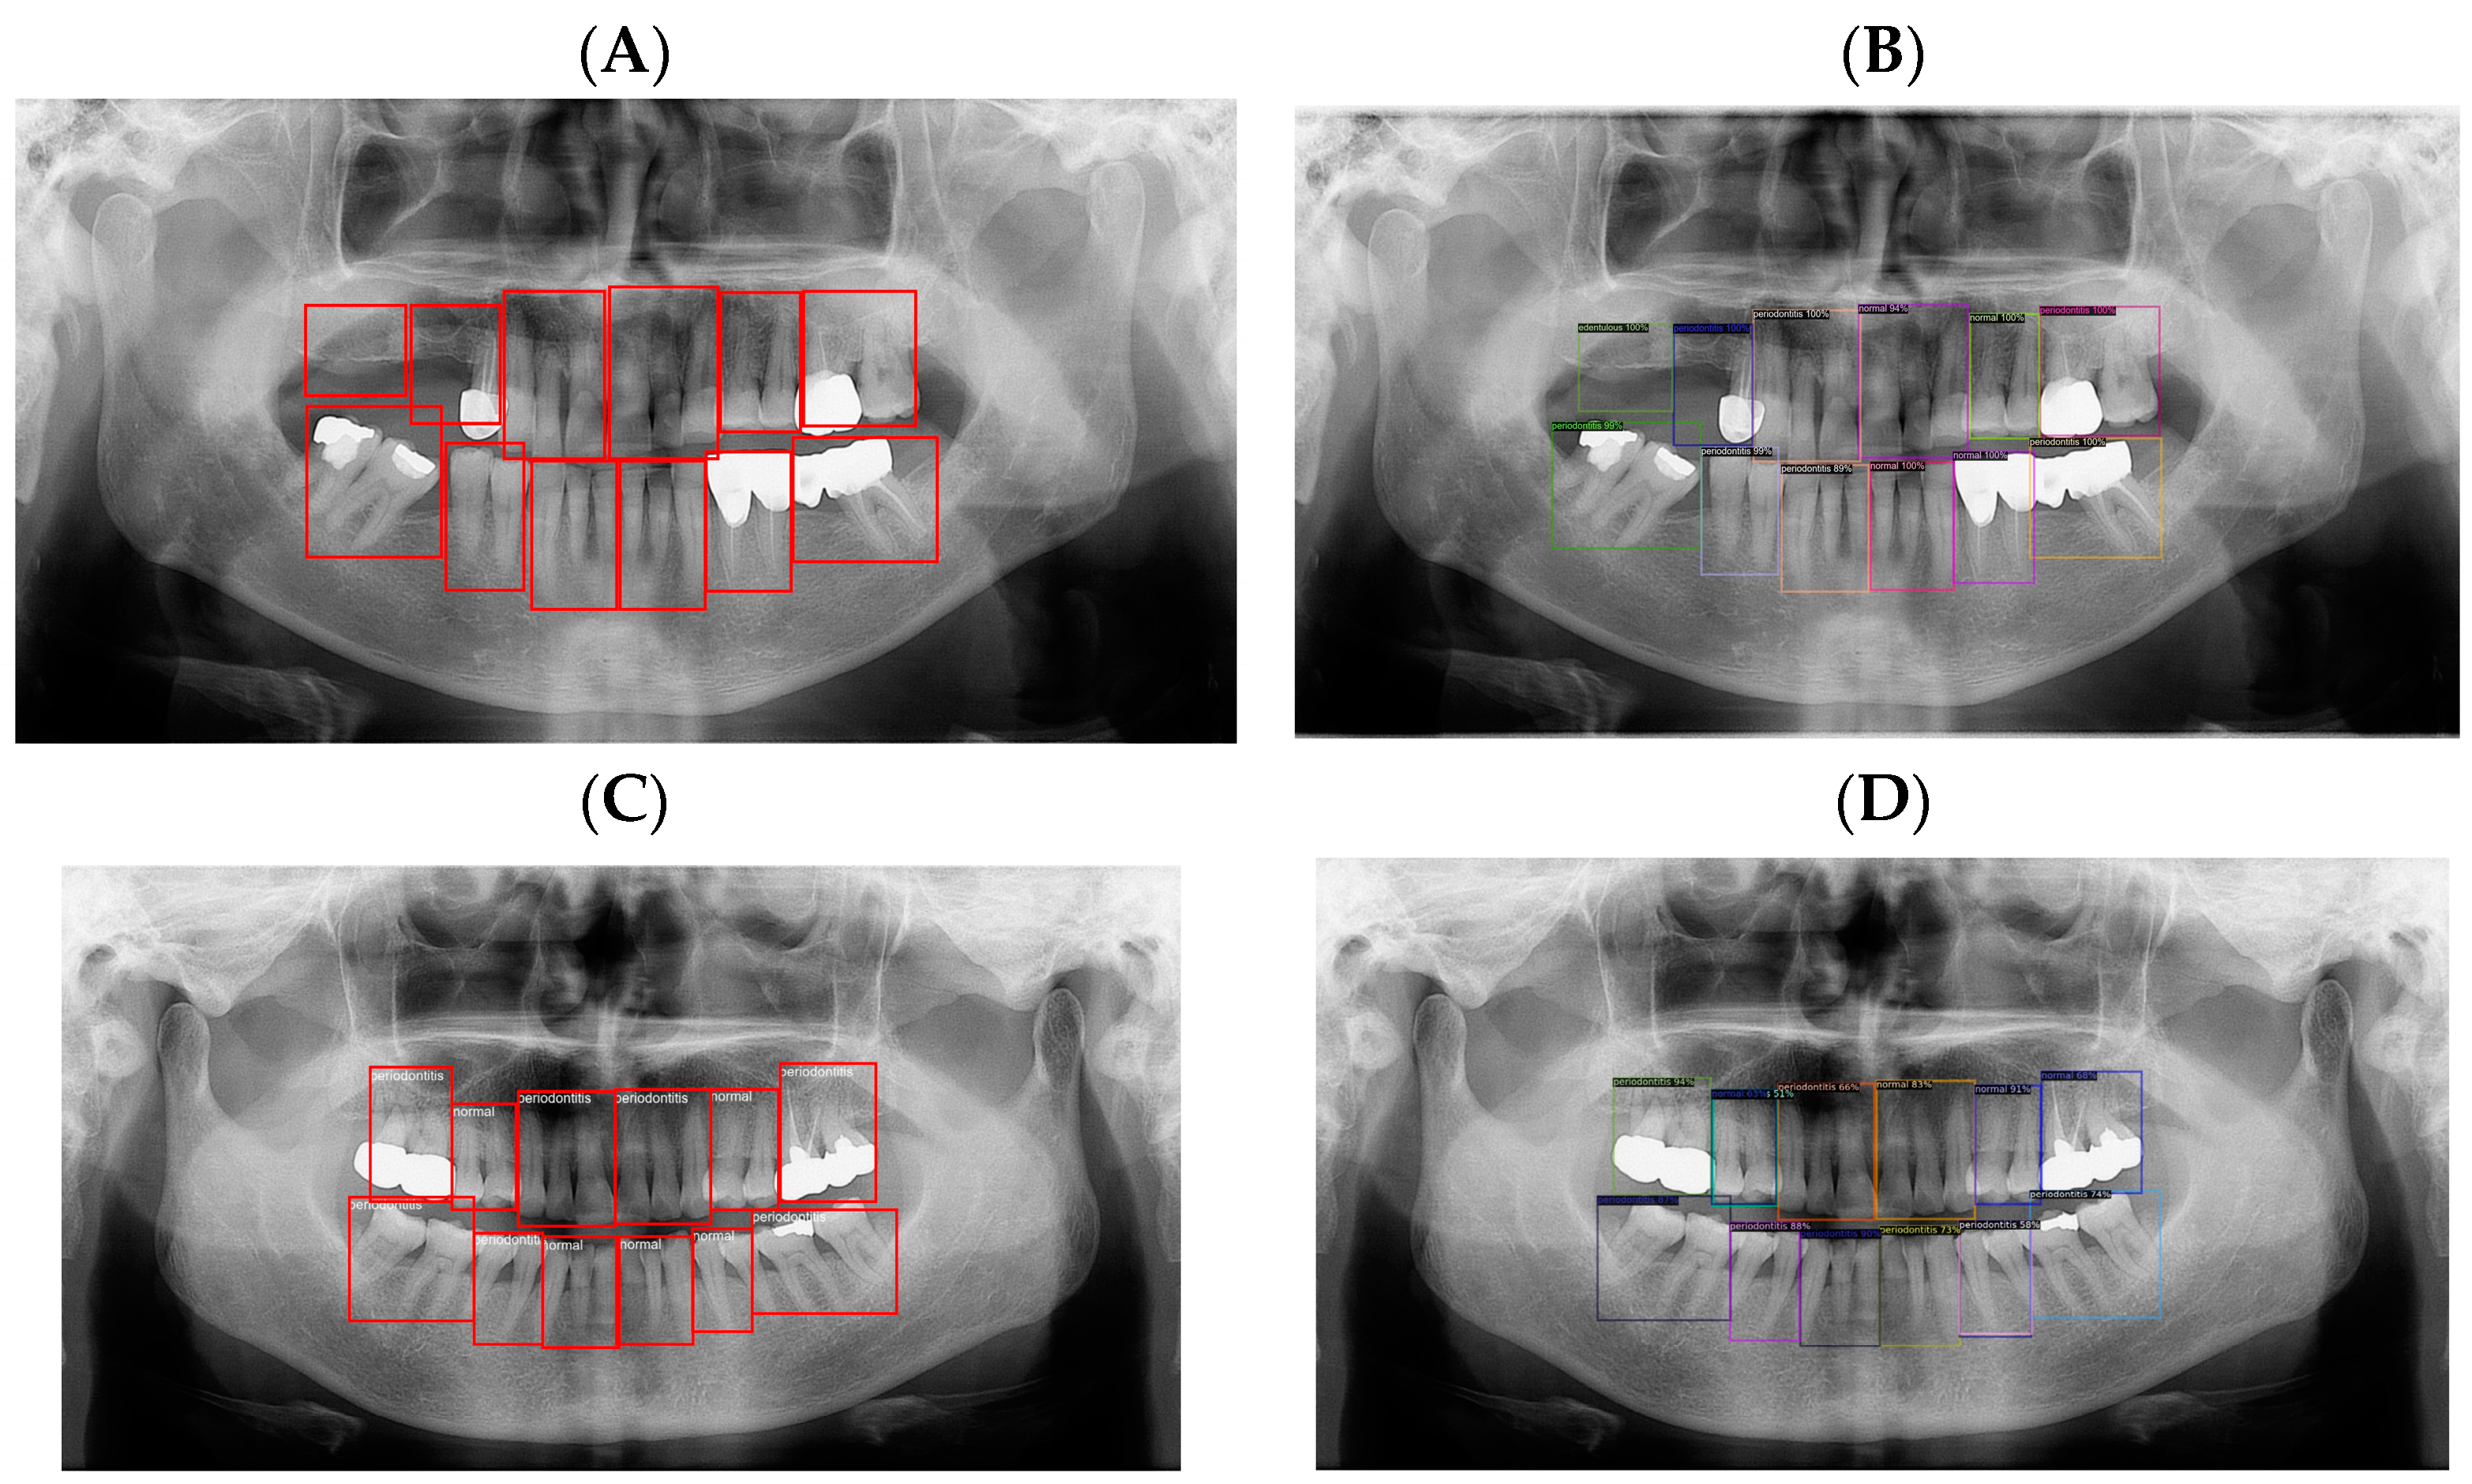

2. Materials and Methods

2.3. Experiment

3. Results